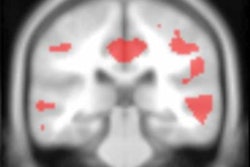

Mecca and colleagues used [11C] UCB-J PET to compare synapse density in 34 people with early Alzheimer's disease with 19 without it. They found high synaptic loss in areas around the hippocampus in people with early-stage Alzheimer's.

"In 34 early Alzheimer's disease compared [with] 19 cognitively normal participants, [11C] UCB-J [PET imaging] ... revealed widespread reductions of SV2A binding in medial temporal and neocortical brain regions," the group wrote. "These reductions were largely maintained after correction for volume loss and were more extensive than decreases in gray matter volume."

Part A shows average synaptic density measured with [11C] UCB-J PET in a group of participants with Alzheimer's disease (right) compared with a group of participants with normal cognition (left). Widespread reduction of synaptic density is present in the group with Alzheimer's disease (AD). Part B shows average amyloid accumulation measured with [11C]PiB PET in a group of participants with AD (right) compared with a group of participants with normal cognition (left). The cognitively normal group is devoid of amyloid and the AD group has extensive amyloid accumulation. Images courtesy of Adam Mecca and Alzheimer's & Dementia: The Journal of the Alzheimer's Association.Mecca and colleagues hope their research could lead to further treatment development, as "quantification of [11C] UCB-J binding to SV2A in Alzheimer's disease may expand our understanding of Alzheimer's pathogenesis and serve as a novel biomarker for diagnosis and therapeutic efficacy," they wrote.